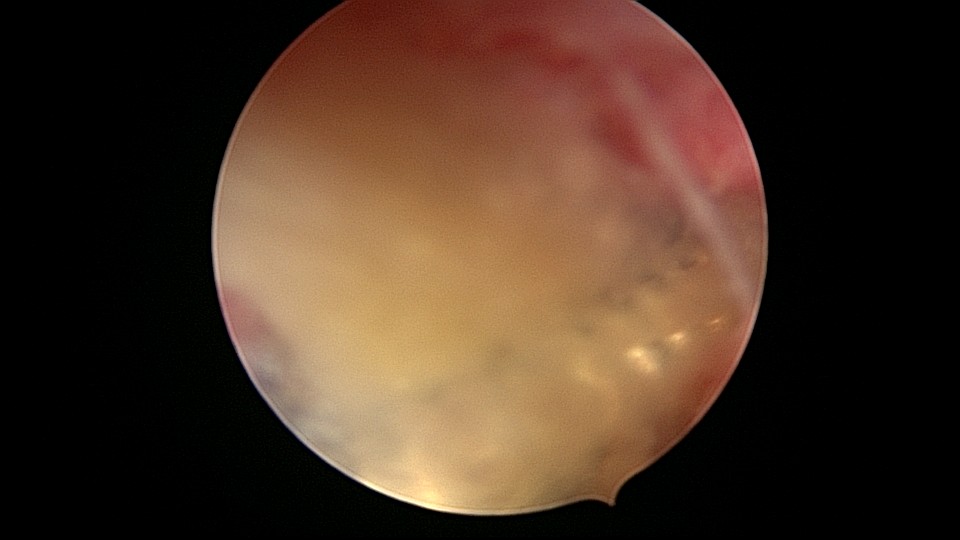

患者58岁,G2P1,顺产1次。安环35年,绝经15年,5年前在外院取环失败。术前B超提示子宫后位,O型环嵌顿,环顶端距宫底0.7cm。宫腔镜术中见阴道口狭小,无法置入窥阴器,宫颈外口狭窄,镜鞘缓慢扩大。宫颈内口粘连,左侧似有一小孔,异物钳扩大小孔,见较多浓稠黄色液体流出,冲洗干净后推进宫腔镜,见2个O型节育环,上面的环取出顺利,下面那个环与宫腔侧壁嵌顿,2次牵拉滑脱,第三次一张一驰松动节育环,再缓慢拉出,宫底见2道环压痕。